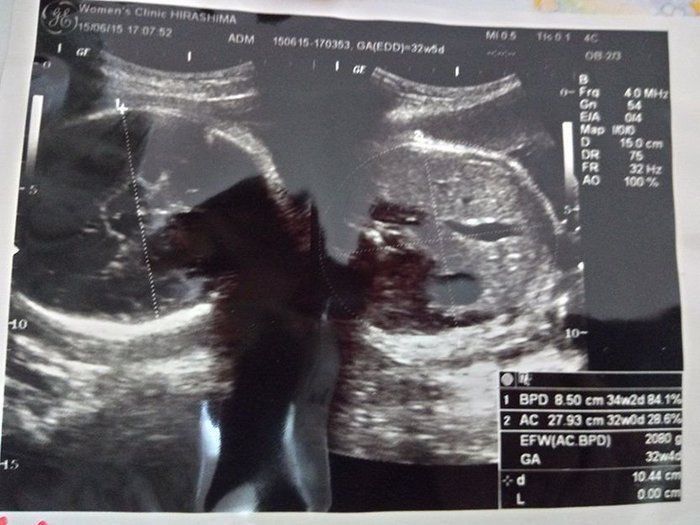

水野谷つむぎさんの妊娠32週目のエコー写真 赤ちゃんの推定体重2080g

宝物の息子とはおなかのなかで対面してた!エコー写真で出会いからこれまでを振り返る

この頃になると股関節痛が酷くなりました。少し歩いただけで、普通には歩けない状態になってしまい、道端でストレッチをしてしのいでいました。